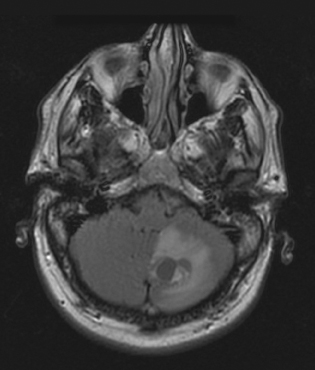

A complete blood cell count, comprehensive metabolic panel, prothrombin time/partial thromboplastin time, and erythrocyte sedimentation rate were normal. An MRl scan of the brain showed a 2 3 1.5 cm left cerebellar cyst with an enhancing mural nodule. There were several smaller, approximately 4 mm, adjacent enhancing nodules. The large cyst was exerting mass effect on the cerebellar hemisphere with partial effacement of the 4th ventricle. There was no reported obstructive hydrocephalus.

The MRI findings were consistent with a pattern associated with von Hippel-Lindau syndrome. Subsequently, an MRI scan of the cervical, thoracic, and lumbar spine was obtained, and a CT scan of the abdomen and pelvis was done. The spinal MRI scan showed multiple cystic lesions. There was a 9 to 10 mm cystic mass of the right dorsal columns at C6-C7, which caused flattening of the spinal cord from C2 to T1. There was a smaller cystic lesion at C1-C2. In addition, there were cystic lesions at T12-L1 and L1-L2, and a 4 to 5 mm lesion at the tip of the conus. The CT scan of the abdomen and pelvis showed no lesions in the kidneys, pancreas, or liver.